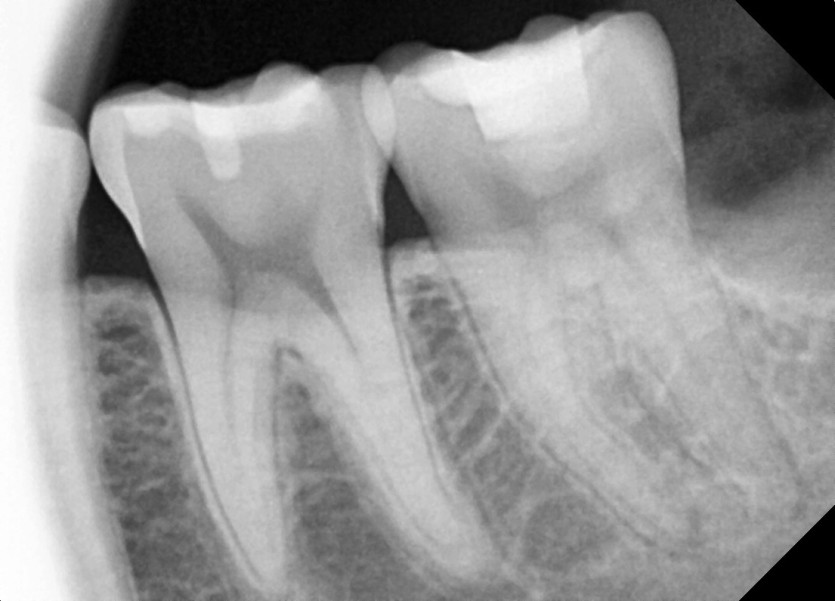

#28,38,48 사랑니 발치

구강 외과 전문의가 당일 발치했습니다.